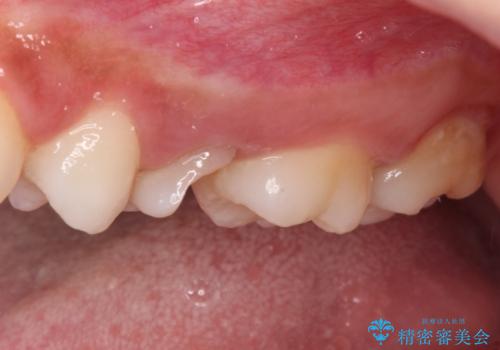

まずは虫歯を除去した上で根管治療を行い、部分矯正により骨内深い位置にまで及んだ健全な部分を引っ張り出すこととしました。

その後骨形成処置を行い、治癒を待って補綴治療を行うこととしました。

かなり深い位置にまで虫歯が及んでいたため、かなりの量を引っ張り出す必要があり、残された歯根は短く小さい状態となりました。